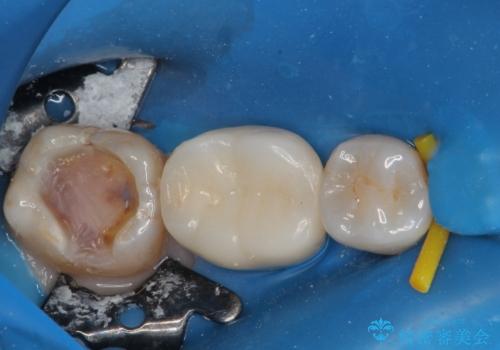

拡大鏡視野下で、銀色の詰め物(メタルインレー)、保険のプラスチック、虫歯の除去を行い、セラミックインレー、フルジルコニアクラウンに適した形に整えました。

歯と歯茎の間に圧排糸と言われる糸を入れてシリコーン印象材にて精密な型どりをしました。

セラミックインレーの装着時には、唾液の侵入を防ぐために、ラバーダム防湿を行いました。